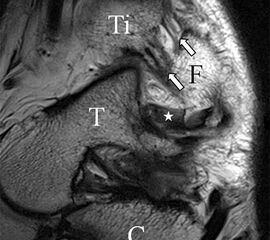

Jedoch findet man sich auch hier mit dem Problem der in den Standard-Projektionen schräg verlaufenden Syndesmose konfrontiert. Der oligofaszikuläre Aspekt der vorderen Syndesmose kann in der axialen Schnittebene eine zum Verwechseln ähnliche Morphologie wie eine Ruptur aufweisen (Abb. 15 b und c). Doppelangulierte Schnitte entlang der Achse (schräg koronar/schräg sagittal) lassen hingegen eine eindeutige Beurteilung der Bandstrukturen zu (Abb. 16) und verbessern die Syndesmosendiagnostik.

Bezogen auf die Transversalebene verläuft die Syndesmose ca. 30° schräg cranio-caudal anguliert (Abb. 15 a). Häufig lassen sich drei Hauptfaszikel differenzieren: das kürzeste superiore, das stärkste mittlere und das längste kaudale Faserbündel. Ein akzessorisches Bündel, das anteriore-inferiore, tibiofibulare Ligament (AITFL) oder auch Bassett-Ligament wird in 80-94% der Patienten nachgewiesen 8. Dies weist einen unmittelbaren Bezug zur anterolateralen Talusschulter auf (Abb. 17). In Kombination mit einer Außenbandinstabilität und konsekutivem, talarem Vorschub kann dieses zu einem Impingement an der anterolateralen Taluskante führen mit nachfolgender chondraler oder osteochondraler Läsion.